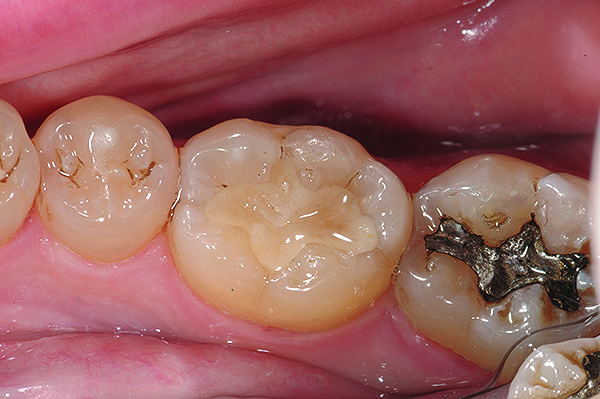

The case demonstrated in Figure 6 through Figure 11 shows the ease with which non-carious Class V lesions can be handled with bulk-filled GIC restorations. Several cervical lesions (abfractions) of significant depth in permanent posterior teeth showed signs of turning carious (Figure 6). The author elected to restore them with the EQUIA technique. For non-carious lesions it is only necessary to freshen the cavity surface and margins with a diamond or carbide bur and to remove any visibly damaged hard tissue. It is then most ideal to remove any smear layer by treating the cavities with a weak acidic solution such as 20% polyacrylic acid (Figure 7). It is important that the clinician not substitute this acidic solution with a conventional phosphoric acid solution or gel used for etching tooth structure prior to resin bonding, as using the conventional solution will remove important mineral content that the GIC requires to bond with chemically. Once the cavities were isolated, a high-viscosity auto-curing GIC was mixed and syringed into the cleaned cavities with a bulk-fill technique (Figure 8). A plastic instrument was then used to condense and shape the material to the cavity walls and margins. The GIC will set in approximately 2:30 seconds to a sufficient level where it is safe to begin adjusting and finishing with rotary instruments. After the restorations were finished, they were coated with a nanofilled, light-cured resin glaze (Figure 9 and Figure 10). The glaze protects the surface of the GIC while it sets completely and enhances the physical strength of the final restoration. The completed GIC restorations (Figure 11) showed excellent esthetics comparable to composite resin.

Fig 9 and Fig 10. After GIC was manually condensed and shaped, a nanofilled resin glaze was liberally applied to the surface of the finished restoration (Fig 9) and light-cured (Fig 10).

Figure 10

Fig 11. Completed bulk-filled GIC restorations showing excellent esthetics and surface smoothness.

Figure 11